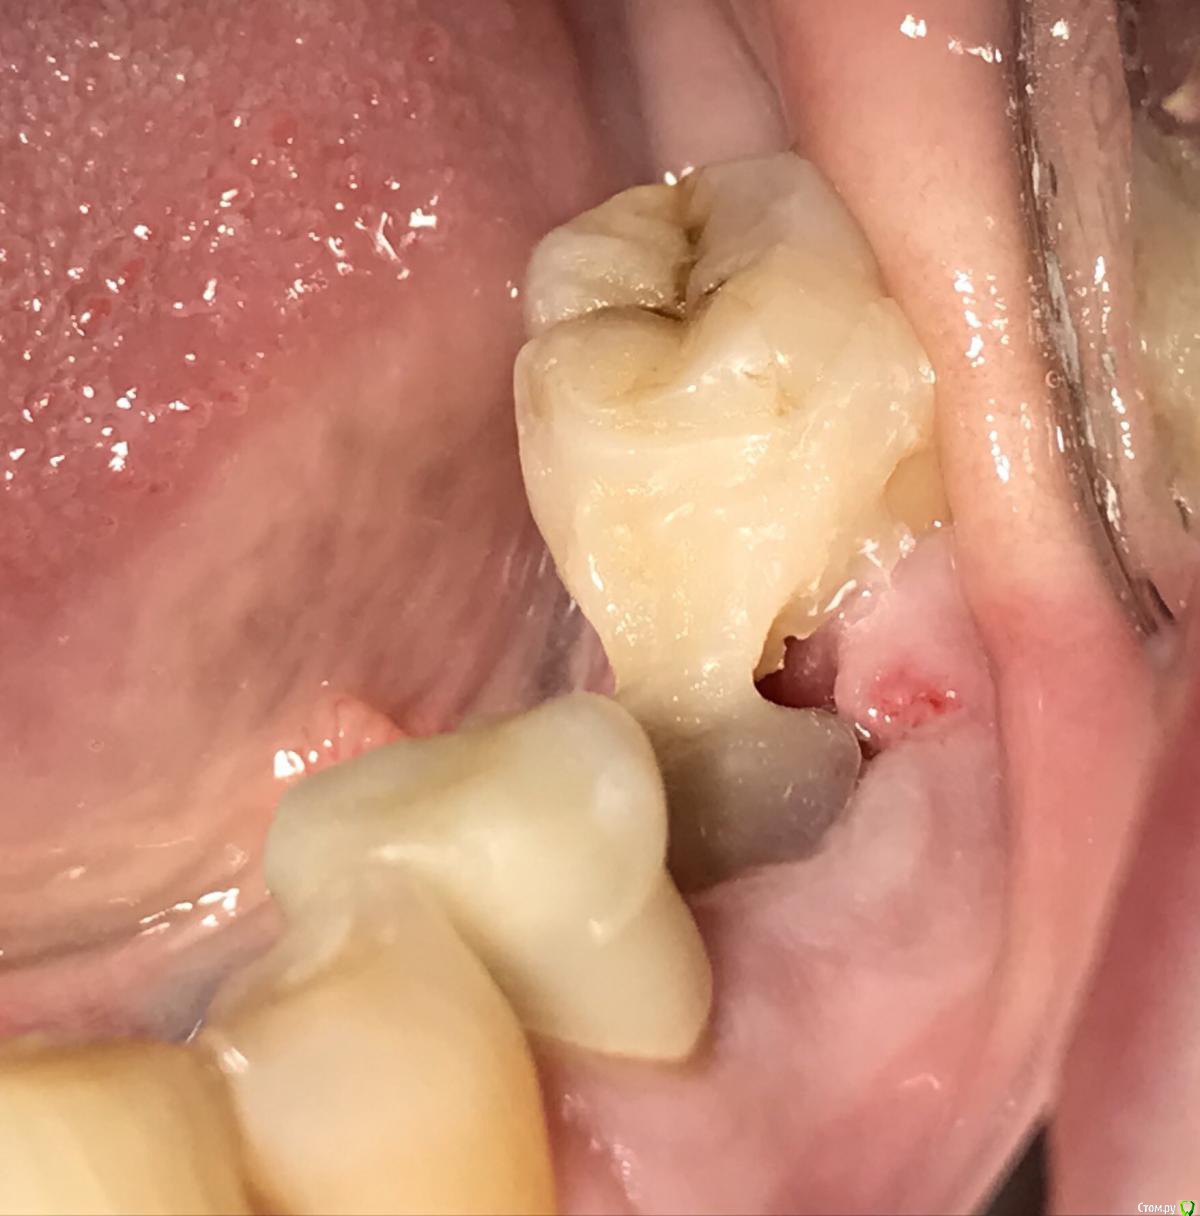

kamranchick Опубликовано 22 апреля, 2018 Поделиться Опубликовано 22 апреля, 2018 Камран, попробуй и узнаешь)))Дык у меня много работ таких на данный момент))) просто пока не раскрывал))))вот из последних) 3 Ссылка на комментарий

kamranchick Опубликовано 30 мая, 2018 Поделиться Опубликовано 30 мая, 2018 Реколы первые 1 Ссылка на комментарий

АнтонТЛТ Опубликовано 30 мая, 2018 Поделиться Опубликовано 30 мая, 2018 (изменено) Чет как-то не ахти. Как думаешь в чем причина? Пробки неподвижны? Изменено 30 мая, 2018 пользователем АнтонТЛТ Ссылка на комментарий

kamranchick Опубликовано 30 мая, 2018 Поделиться Опубликовано 30 мая, 2018 Чет как-то не ахти. Как думаешь в чем причина? Пробки неподвижны?Пробки намертво приклеены.Причина не знаю в чем(Это провал, ибо пациент готовится на имплантацию уже.Тут даже 3.5 с трудом проходит 1 Ссылка на комментарий